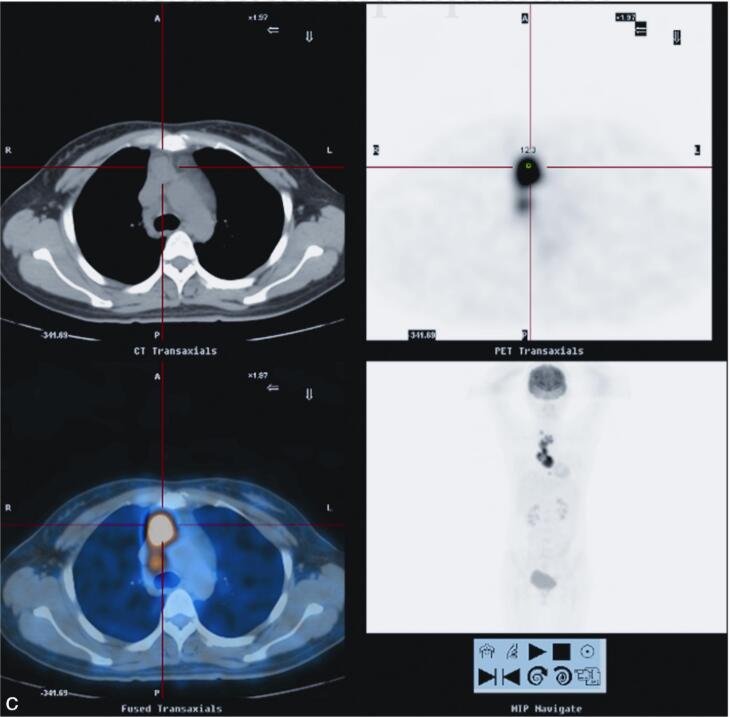

2010年5月10日于我院18F-FDG PET/CT检查:纵隔内及右肺上叶前段病变,代谢异常升高,考虑慢性感染性疾病可能性大(结核肉芽肿?),请结合临床,进一步完善结核相关检查,必要时纵隔镜活检以除外恶性病变(图2)。

图2 PET/CT示右肺上叶前段纵隔旁见高密度实变影,内见充气支气管影,FDG代谢放射性分布异常浓聚(SUVmax=12.4)。前纵隔内见软组织密度肿块影,最大截面积约为5.2cm×3.0cm,其内密度不均,见低密度坏死区,实质区FDG代谢放射性分布异常浓聚(SUVmax=15.0),邻近心包;右锁骨上、前上纵隔、主肺动脉窗,气管叉下(其内见钙化灶)及心包右旁见肿大淋巴结影,部分融合趋势,FDG代谢放射性分布异常浓聚